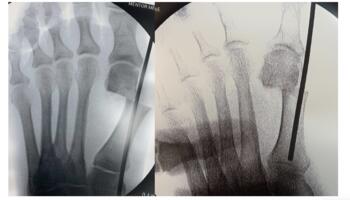

Metatarsal Head Translation. First, shift the metatarsal head laterally by inserting an elevator or hemostat (see third photo above) into the medullary canal. Maintaining the elevator or hemostat parallel to the long axis of the first metatarsal during the shift will prevent deviation of the capital fragment in the sagittal plane.

Next, the surgeon should rotate the hallux in a varus position to correct the frontal plane deformity (see fourth photo above). Once the metatarsal head is translated and the frontal plane is reduced, one can hold the reduction with the non-dominant hand. A large K-wire or Steinmann pin should capture the medial capsular tissue at the hallux and metatarsal head. This step can be performed prior to obtaining reduction of the metatarsal head to allow for easier placement into the metatarsal shaft. Following reduction, the surgeon will advance this wire intramedullary to the metatarsal base or across the first TMTJ for additional stability (see fifth photo above). Another method to maintain correction is to provisionally fixate the first metatarsal head to the second with a K-wire, with the intermetatarsal angle and tibial sesamoid position corrected. Consider lateral capsular or fibular sesamoid release if reduction is difficult. Also, consider an MIS Akin if the hallux remains in valgus or when there is an intrinsic deformity to the digit.

The surgeon may shift the capital fragment as much as necessary as long as there is some contact maintained between the metatarsal shaft and the head. It is possible to plan the amount of translation necessary on the preoperative X-ray, based on the position of the fibular sesamoid. In our experience, the lateral cortex of the metatarsal head should end up in a position just lateral to the fibular sesamoid on the preoperative X-ray. The gap between the lateral metatarsal head and metatarsal shaft will consolidate over time (see sixth and seventh photos above). A multitude of advanced options for fixation exist, including, but not limited to headless compression implants (see seventh and ninth photos above) and plate-intramedullary hybrid devices (see sixth photo above). Intramedullary devices do require a slightly larger incision for appropriate placement.